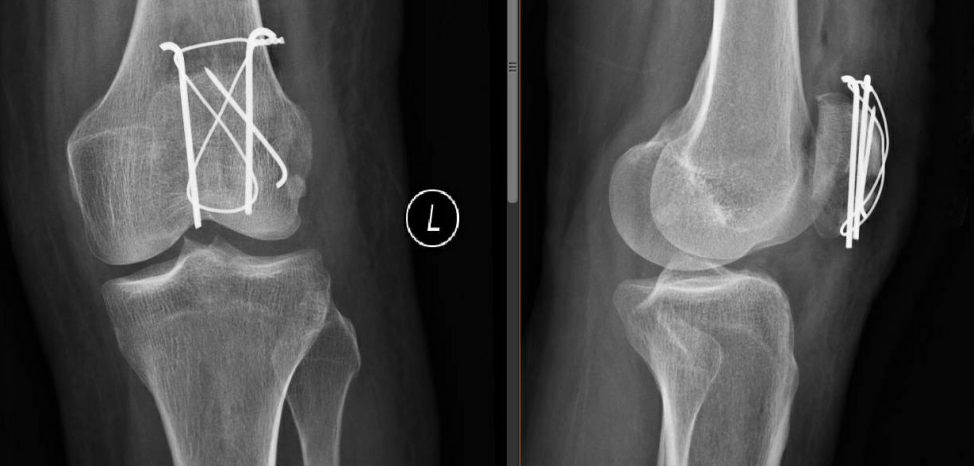

術(shù)后第二天復(fù)查左髕骨X線提示:左髕骨骨折術(shù)后改變,可見金屬內(nèi)固定器影,斷端對(duì)位對(duì)線佳,骨小梁尚規(guī)則,左膝關(guān)節(jié)在位,關(guān)節(jié)間隙尚可。

那如果髕骨骨折了該怎么辦呢?首先要明白髕骨骨折了重要的是要恢復(fù)其關(guān)節(jié)面的平整,關(guān)節(jié)的活動(dòng),恢復(fù)力的傳導(dǎo),關(guān)節(jié)的穩(wěn)定性。所以手術(shù)調(diào)節(jié)就顯得尤為重要。我為本例患者采用了“髕骨骨折切開復(fù)位張力帶鋼絲內(nèi)固定術(shù)”進(jìn)行調(diào)節(jié),其主要優(yōu)點(diǎn)在于其符合髕骨生物力學(xué)特點(diǎn)(類似尺骨鷹嘴),簡(jiǎn)單可靠,體積小,可使患者早期進(jìn)行功能鍛煉,并且有很高的愈合率。除了這種手術(shù)調(diào)節(jié)方法外,還有其它類型的手術(shù),但不管哪種調(diào)節(jié)方式,重要的是,如果不慎髕骨骨折了,就應(yīng)該立刻到醫(yī)院就診進(jìn)行調(diào)節(jié),避免耽誤調(diào)節(jié)時(shí)間。